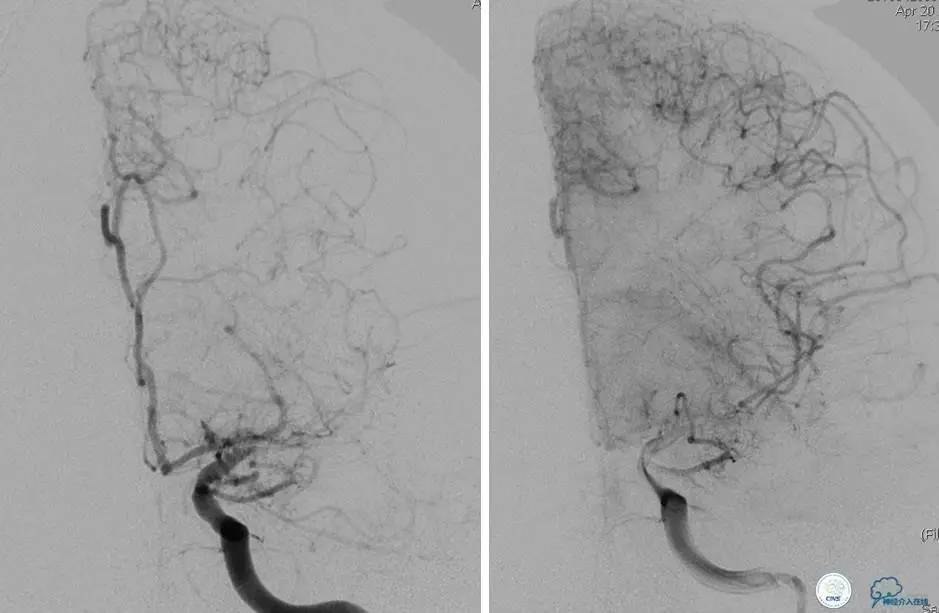

患者:58岁男性,反复头晕、肢体无力3月,当地造影见多发颅内动脉狭窄、闭塞,转来我院。

▼首先行颈动脉CTO开通术,手术顺利,Wallstent支架。

▼1周后行右侧椎动脉V4段CTO开通术。

▼微导丝穿过狭窄段,微导管造影,小球囊预扩张,2mm。

▼根据血管情况选择较大球囊再次预扩张。

▼置入2枚Wingspan支架,手术成功。

▼术后即刻CT,梗死灶内再灌注出血。

患者无症状,中性治疗。4月21日电话随访,一般情况好,当地CT示出血吸收期。